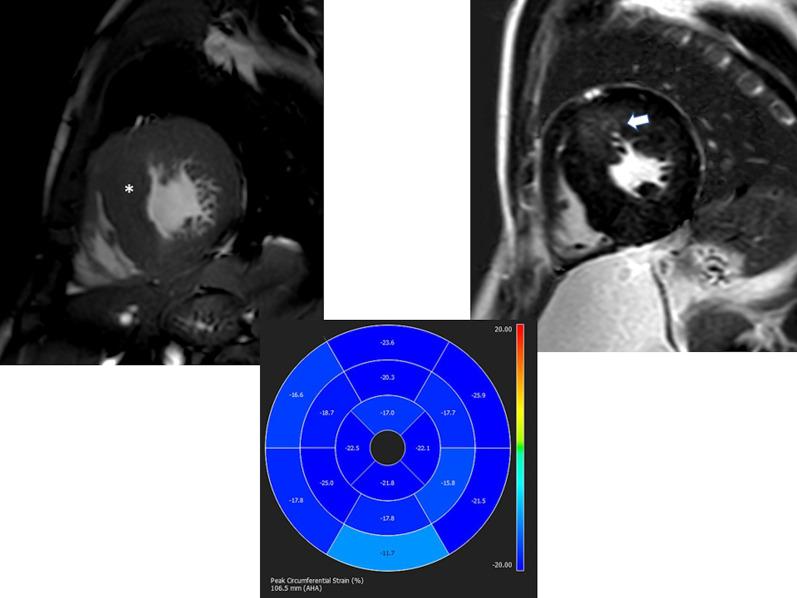

Cardiovascular magnetic resonance (CMR) has been utilized in the management and care of pediatric patients for nearly 40 years. It has evolved to become an invaluable tool in the assessment of the littlest of hearts for diagnosis, pre-interventional management and follow-up care. Although mentioned in a number of consensus and guidelines documents, an up-to-date, large, stand-alone guidance work for the use of CMR in pediatric congenital 36 and acquired 35 heart disease endorsed by numerous Societies involved in the care of these children is lacking. This guidelines document outlines the use of CMR in this patient population for a significant number of heart lesions in this age group and although admittedly, is not an exhaustive treatment, it does deal with an expansive list of many common clinical issues encountered in daily practice.

心血管磁共振(CMR)在儿科患者的管理和护理中已经应用了近 40 年。它已经发展成为评估最小的心脏的宝贵工具,用于诊断、介入前管理和随访。尽管在许多共识和指南文件中提到,但在儿科先天性心脏病和后天性心脏病领域,目前还缺乏一份由众多参与儿童护理的学会共同认可的、最新的、独立的、针对 CMR 使用的大型指南。本指南文件概述了 CMR 在该年龄段的许多心脏病变中的应用,尽管不能说是详尽的治疗方法,但它确实涉及了在日常实践中经常遇到的许多常见临床问题的广泛列表。